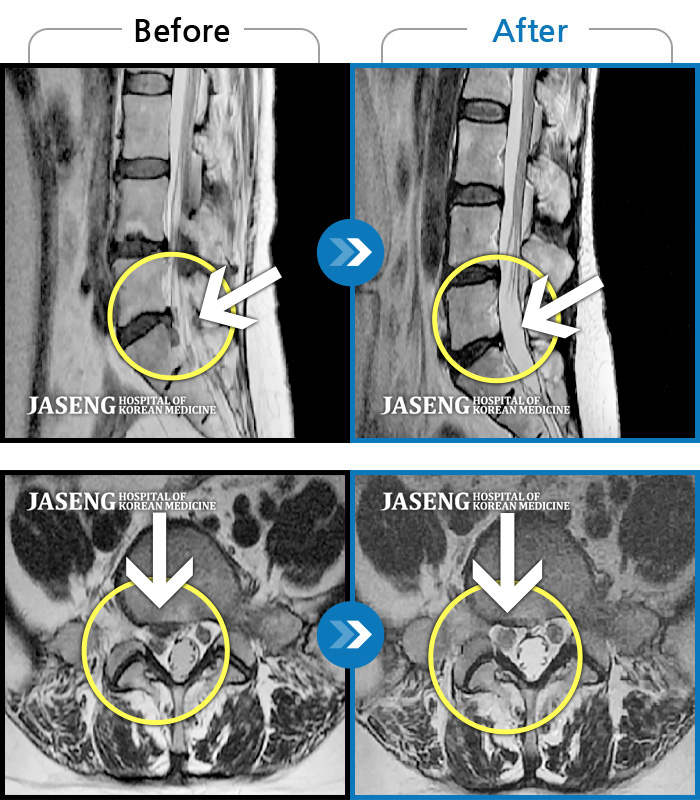

허리디스크

해운대 · 김상돈 원장

아래쪽 허리와 우측 골반에 통증이 있었습니다.

촬영시기

2019.08.26 ~ 2025.08.09

2025.08.14